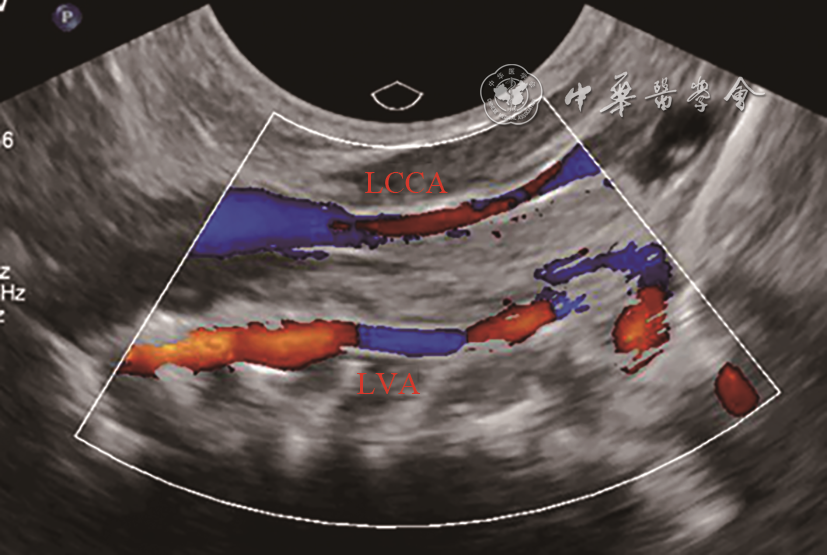

新生儿,足月顺产,Apgar评分9分;产前羊水穿刺正常。2019年10月在成都市第五人民医院分娩后发现左手掌指端紫绀;体格检查:心肺听诊胸骨左缘第二肋间疑似连续性杂音;床旁心脏超声:右位主动脉弓,左位动脉导管未闭,大动脉水平右向左分流。出生后第4天,左手掌紫绀消失。复查心脏超声:心脏房室大小正常,房室连接、心室大动脉连接关系正常;主动脉弓位于气管右侧,弓上可见3个分支,依次为左颈总动脉、右颈总动脉、右锁骨下动脉(图1);左肺动脉起始部可见宽约0.4 cm管型动脉导管未闭,彩色多普勒显示导管内左向右分流(图2);追踪导管走行,导管与左锁骨下动脉延续(动态图1);左锁骨下动脉与主动脉弓无连接关系。进一步行颈部血管超声检查左侧椎动脉,可见椎动脉血流反向(图3)。超声诊断:右位主动脉弓,孤立性左锁骨下动脉,动脉导管未闭,先天性左锁骨下动脉窃血,先天性肺动脉窃血。患儿一般情况良好,于出生后第7天出院,嘱其3个月后复查心脏超声。

注:LCCA为左颈总动脉;LVA为左椎动脉

Leutmer等8文献回顾表明,超过半数(59%)的孤立性左锁骨下动脉伴发紫绀型先天性心脏病,其中以法洛四联症(tetralogy of Fallot,TOF)最常见。CT和数字减影血管造影(digital subtraction angiography,DSA)可以很好显示左锁骨下动脉起源以及与主动脉弓的关系,是诊断ILSA的金标准9, 10, 11。本例患儿CTA显示左锁骨下动脉起始端线状变细并靠近左肺动脉,左肺动脉起始部发出鸟嘴样动脉导管残端是孤立性左锁骨下动脉特征性改变。超声心动图可以比较准确地诊断心内结构畸形,但对于不伴心内结构畸形的ILSA超声诊断存在局限性。特别是动脉导管闭合后,由于纵隔遮挡及肺气干扰,很难显示左锁骨下动脉的起源;超声显示同侧椎动脉血流反向有助于提示本病。不过,通过本例患儿发现,新生儿纵隔透声性明显好于成人,使得超声可以更清晰显示主动脉弓上分支起源情况,这有助于明确本病诊断。ILSA患儿胸骨上窝主动脉弓长轴切面,可见异常排列的3个主动脉弓分支,依次为左颈总动脉、右颈总动脉、右锁骨下动脉。当合并动脉导管未闭时,在高位大动脉短轴切面,可以直接显示左锁骨下动脉通过动脉导管与左肺动脉的唯一连接关系。同时,彩色多普勒可以观察椎动脉血流方向以及左锁骨下动脉与肺动脉之间导管内血流分流方向,进一步明确是否存在锁骨下动脉窃血或肺动脉窃血。